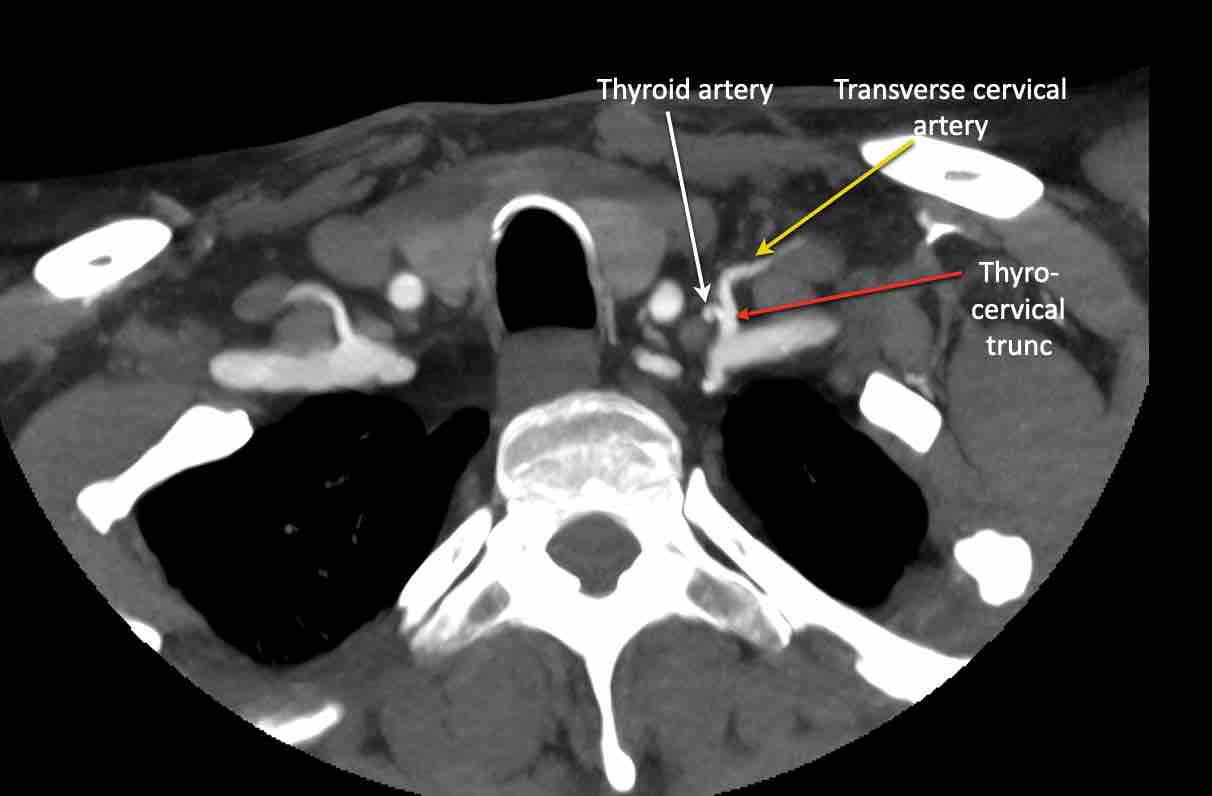

Động mạch cổ ngang

Cuộn qua các hình ảnh để xem giải phẫu của động mạch cổ ngang.